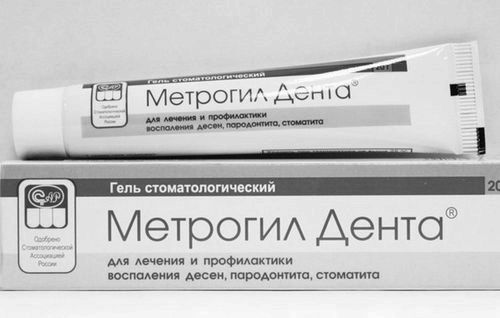

Метрогил дента. До складу даного лікарського засобу входить відомий антисептик Хлоргексидин, а також антибіотик «Метронідазол, тому без призначення лікаря не можна застосовувати цю мазь, особливо якщо у вас є алергія на деякі види протимікробних препаратів.